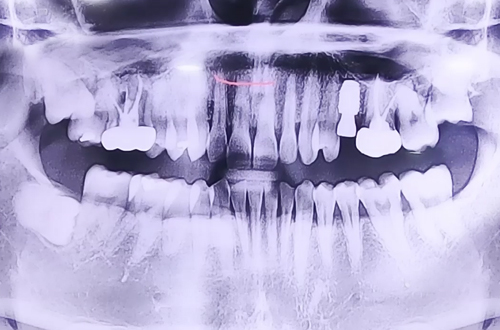

왼쪽 위 부러진 어금니 임플란트

BEFORE

왼쪽 위 어금니 쪽에 극심한 통증을 호소하신 환자분이십니다.

X-ray 상에서는 치아에 큰 이상이 없어 보였지만 치아를 자세히 검사해 보니 왼쪽 위 어금니가 반으로 쪼개진 상태로 발치 이후 즉시 임플란트 치료를 진행하였고 뼈가 비어있는 부분들은 임플란트 주변 뼈이식을 진행해 드리면서 마무리해드렸습니다.

현재는 임플란트 위로 치아머리를 만들기 위한 부품을 끼워 놓은 상태이며 추후 임플란트가 단단히 자리 잡고 난 뒤 보철이 완성되면 다음 진료일지로 찾아뵙도록 하겠습니다! ^^